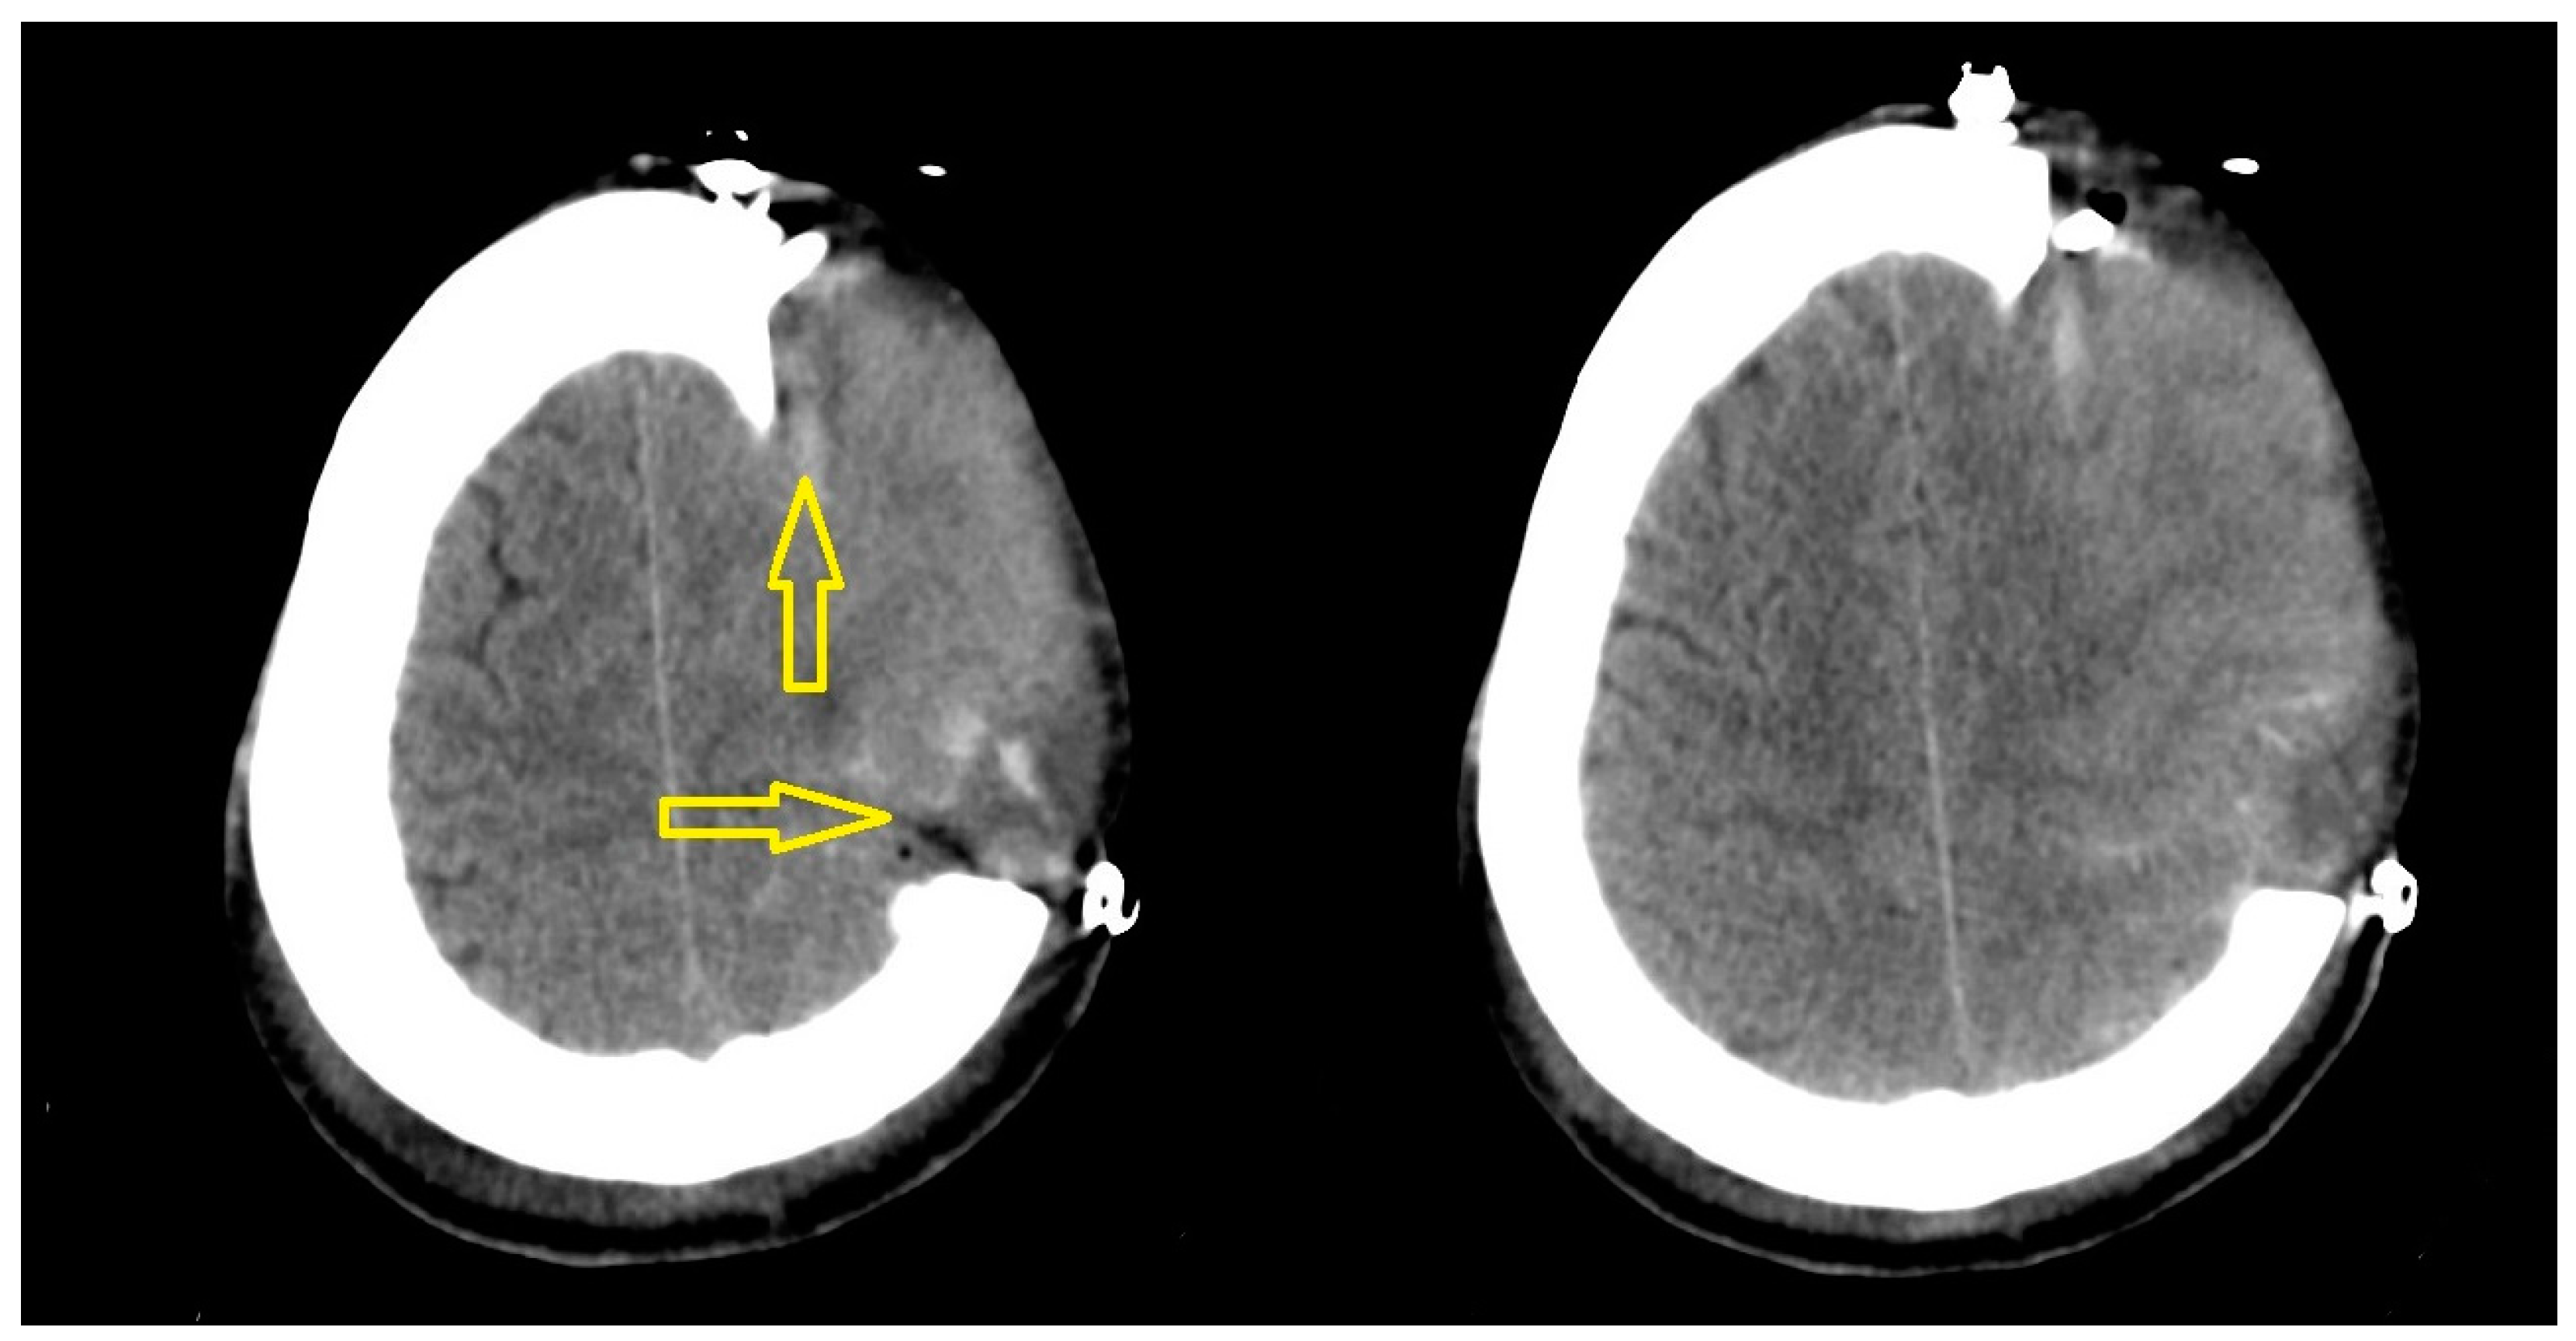

| Shear bleeding complications | 14 |